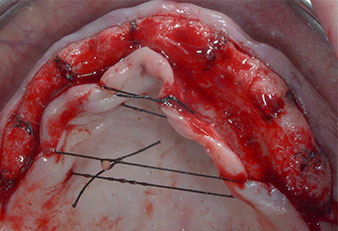

Drei Jahre später war es Zeit für eine gleichartige Oberkieferprothese. Basierend auf der DVT-Planung wurde durch Verwendung kurzer Implantate eine Sinusaugmentation vermieden und die geplanten Implantatpositionen wurden mit einer Bohrschablone auf den Kieferkamm übertragen (Abb. 1 und 2).

Abb. 2: Nach dem Kieferkammschnitt und der Präparation der Mukoperiostlappen werden die Implantatpositionen auf den Knochen übertragen.

Wegen des relativ harten Knochens (D2) an den Positionen 11 und 21 wurden die 10 mm langen Implantatlager in diesem Bereich abschließend mit einem 4-mm-Spiralbohrer, dem chirurgischen Winkelstück WS-75 L von W&H und dem W&H Implantmed Implantologiemotor in Verbindung mit dem optionalen W&H Osstell ISQ module präpariert. Im Gegensatz dazu wurde der weiche Knochen der Implantatlager im Seitenzahnbereich mit dem Piezomed I3P auf den abschließenden Durchmesser von 3 mm erweitert. Die Implantate wurden dann transgingival eingesetzt, die Einheildauer betrug drei Monate (Abb. 6-10). Die vorhandene Prothese wurde auf vier provisorischen Implantaten abgestützt (Abb. 8).